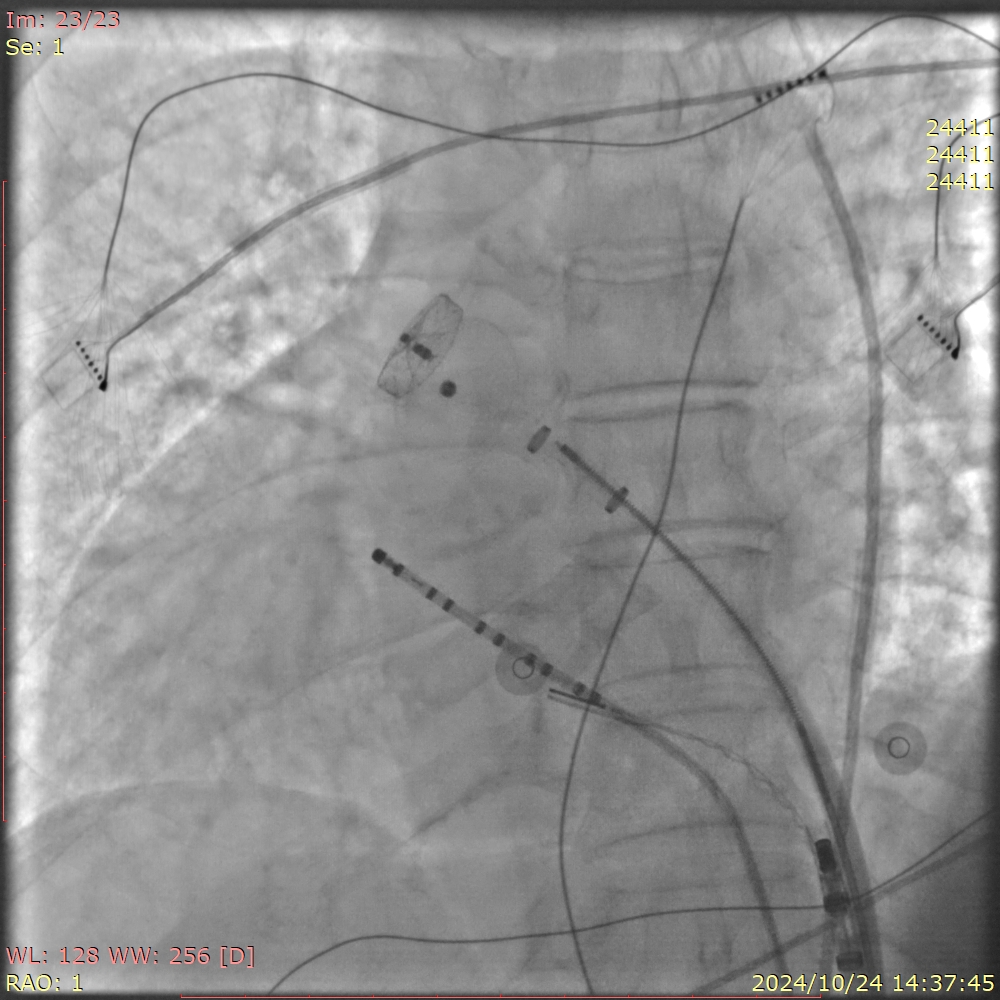

手术过程中,王洪涛教授亲自操刀,充分利用CARTO 3三维标测系统,实现了精准定位和消融,成功为患者实施了房颤射频消融术。随后,团队又克服了镜面右位心带来的操作困难,使用新一代国产左心耳封堵器LACbes成功完成了左心耳封堵术,有效预防了卒中的发生。王洪涛教授解释:“房颤射频消融术能够消除房颤的症状,而左心耳封堵术则能够闭合房颤患者血栓发生的根源部位,两者结合能够大大降低患者的卒中和出血风险。”

整个手术过程历时数小时,团队凭借精湛的技术和丰富的经验,确保了手术的顺利进行。术后,患者生命体征平稳,无并发症发生,恢复情况良好。王洪涛教授对手术效果表示满意:“患者的恢复情况非常理想,这标志着我们医院在复杂心律失常疾病治疗方面迈上了新的台阶。”

房颤是一种常见的心律失常疾病,其最大的危害在于形成血栓导致脑中风。对于镜面右位心合并房颤的患者来说,传统治疗方法往往难以兼顾抗凝和减少出血风险的需求。此次房颤射频消融联合左心耳封堵一站式手术的成功实施,为患者提供了一种全新的治疗选择。